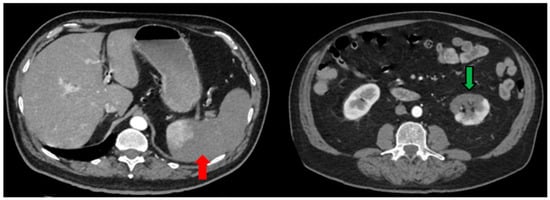

| Day 43 | CTPA: Residual ground-glass opacity lesions, fibroatelectacic lesions at the right lower and middle lobe, traction bronchiectasis at right middle lobe and lingula of left lobe. No presence of thrombi at the thoracic aorta. Abdominal and pelvic CT scan: Splenic and renal infarct (along with renal cortical thinning) are depicted again. Re-tunelling of the splenic vein. |